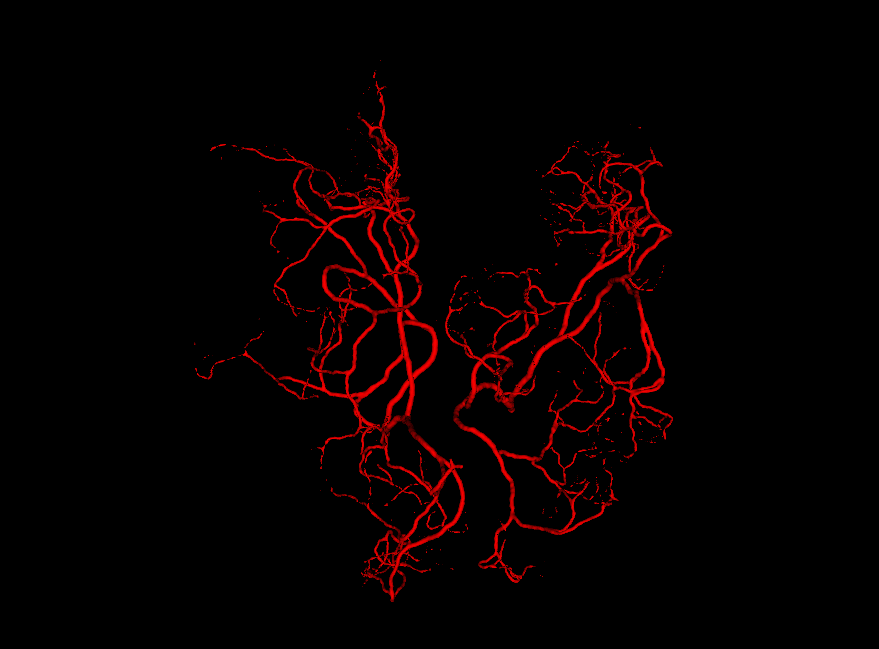

Figure 3.3: Generated vessel structures with spatial target growth incentive. The target volume was a vessel density atlas created by averaging the ground truth of patients in our data set.

An approach was also introduced to make the global vessel distribution mimic the one found in the brain. The brain arterial system is designed to supply the entire brain, yet the current structure described so far grows away from the root node and is unlikely to meaningfully fill the volume of the brain once rendered. To solve this issue, a density atlas was created out of the patients scans in our data set to assign a volume with probabilities of an artery being present.

This volume was turned into binary values depending on whether a region had a probability density above a certain threshold. This transformation proved to be helpful to prevent all neighbouring vessels within a region to cluster into the same high-probability regions, and instead spread evenly out. When a leaf node was created (except in the bifurcation case), the surrounding region to the nodes position was sampled in the atlas. The sampled point with the highest value smaxsubscript𝑠𝑚𝑎𝑥\vec{s}_{max} was then used to create a target vector t=smaxpc𝑡subscript𝑠𝑚𝑎𝑥subscript𝑝𝑐\vec{t}=\vec{s}_{max}-\vec{p}_{c} towards which to rotate the new child’s dcsubscript𝑑𝑐\vec{d}_{c}. After the rotation, the resulting vector is normalized to have the same length as its parent:

To incentivize vessels to spread out, every time a node is created the neighboring region around the node in the atlas was reduced in value. The neighboring region was in the form of a sphere around the node’s position pcsubscript𝑝𝑐\vec{p}_{c}. The neighborhood radius was linearly proportional to the radius of the node rcsubscript𝑟𝑐r_{c}.

Another use of the vessel atlas is to determine if a node is out of bounds. This is done by checking if the atlas has a value of 0 at the node’s position. If a leaf node is too far out of the brain, the branch is discontinued (the leaf will never be selected to spawn a child). On top of this, in order to make the overall structure more realistic, a different atlas was used for each of the two hemisphere root nodes. Such atlas would only have non-zero values for one brain hemisphere. This causes the resulting vessel structures to no longer cross over between hemispheres. A resulting example structure can be seen in Figure 3.3.